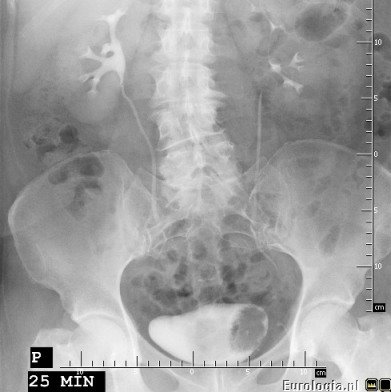

Urografia

Urografia straciła nieco na znaczeniu w diagnostyce guzów pęcherza moczowego po wprowadzeniu USG. Guzy pęcherza czasami są widoczne na zdjęciach urograficznych jako ubytek wypełnienia w świetle pęcherza moczowego.